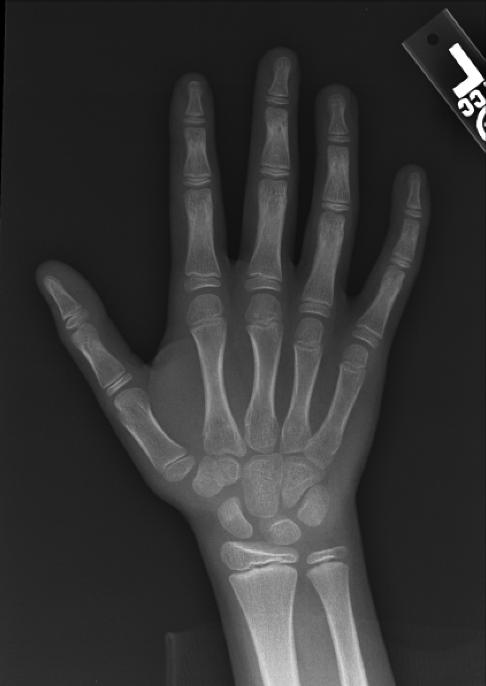

Por último, valoramos la edad ósea por medio de una radiografía de la mano no dominante (con la que no se escribe). Esta nos permite saber el grado de maduración corporal y del esqueleto, para saber el potencial de crecimiento que tiene el cuerpo. Esta se realiza en cualquier centro radiológico y es recomendable traerla a la consulta para abreviar tiempo.